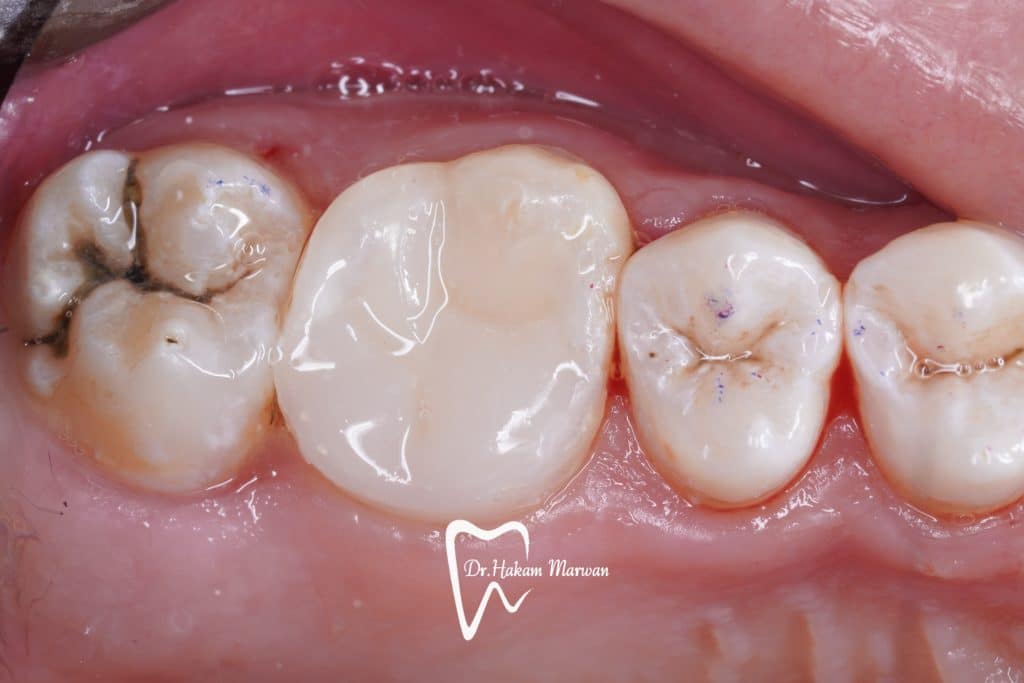

UL6 with SAP and deep palatal caries.

Caries removal and cleaning to determine the margin height then margin elevation as a pre endo build up under rubber dam isolation, endodontic treatment in the same visit to minimize flar up and direct restoration was done in the second visit.